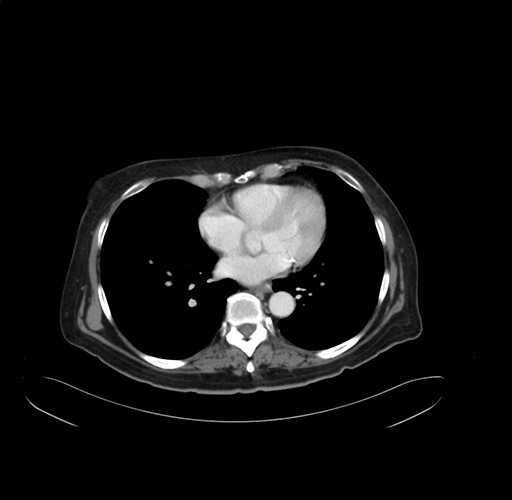

Pre-Chemo: Axial Venous

Axial Venous